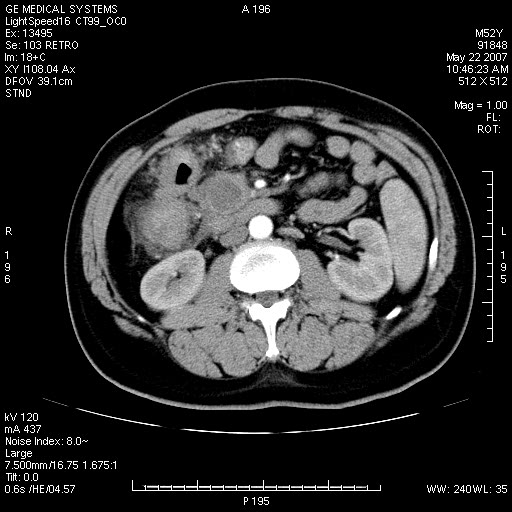

以下是引用余辉在2007-5-22 20:12:00的发言:[br]升结肠管壁明显增厚,增强有静脉期持续增强,结合患者病史,考虑结肠癌可能性大,临近脂肪影密度增高,混浊,恐有肠系膜浸润转移,建议镜检

以下是引用dyqct在2007-5-22 20:43:00的发言:[br]支持结肠肝曲占位性病变(浸润型结肠癌可能性大)。胆总管下端扩张,原因待查。

以下是引用gaoxiao在2007-5-22 20:49:00的发言:[br]考虑升结肠癌向周围侵犯,胰头钩突受侵。